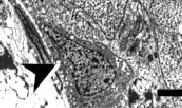

De zaadvormende cellen bij de clenbuterolvarkens waren gedegenereerd. Je ziet zo'n afgetakelde cel bij de pijlpunt.